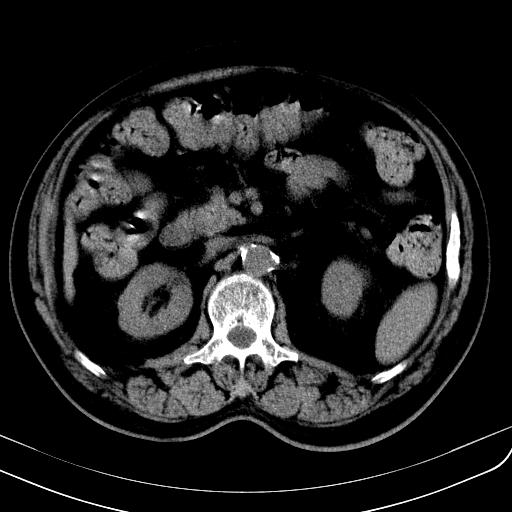

胃底靠近胃大弯处可见一圆形软组织影,直径为3.45cm,ct值约为30.1hu

边缘光滑,密度均匀,良性占位,首先考虑平滑肌瘤。

边缘光滑,密度均匀,良性占位,首先考虑平滑肌瘤。其实平滑肌瘤也是间质瘤的一种